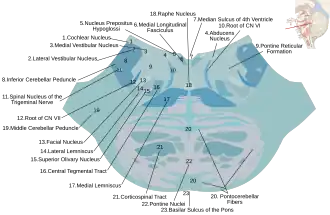

Nuclei of origin of cranial motor nerves schematically represented; lateral view. Cross section of the lower pons showing the facial motor nucleus and part of the root of the facial nerve.

Cross section of the lower pons showing the facial motor nucleus and part of the root of the facial nerve.